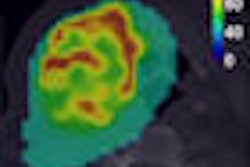

In comparing the results for differentiating between malignant and benign soft-tissue tumors, FDG-PET/CT and MRI showed similar efficacies in sensitivity, specificity, positive predictive value (PPV), and negative predictive value (NPV). (See chart below).

Differentiating between malignant and benign soft-tissue tumors

Kong noted that the maxSUV for malignant soft-tissue tumors was 13.2, while the maxSUV for benign soft-tissue tumors was 4.8.